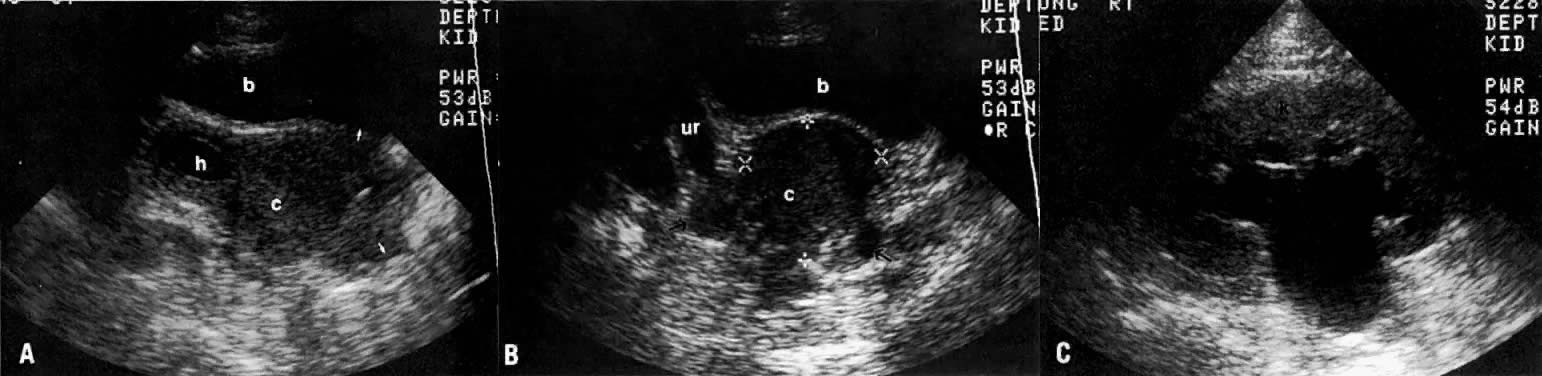

In locally confined disease, a cervical mass may be seen by ultrasound (Fig. 5B and C). In locally advanced disease, the cervix may become diffusely enlarged, inhomogeneous, and irregularly marginated (Fig. 6A and B).

Fig. 6. Advanced cervical carcinoma. Sagittal ( A) and transverse ( B) sonograms of the pelvis show a markedly enlarged, irregular cervical mass invading both parametria ( black arrows ), encasing the right ureter laterally, and obliterating the fat planes ( white arrows) between the cervix and bladder anteriorly, and cervix and rectum posteriorly. The mass is obstructing the uterus, causing hydrometras. Sagittal sonogram ( C) of the right kidney shows moderate hydronephrosis. ( c, cervical mass; ur, ureter; b, bladder; h, hydrometras; k, kidney.)

The presence of hydrometras should raise the suspicion of cervical or endometrial carcinoma. It is best demonstrated by ultrasound (see Fig. 6A), but can be seen by both MRI (Fig. 7) and CT (Fig. 8).11,12 This finding, however, is nonspecific because it can also be seen in benign cervical strictures caused by either previous cervical inflammation (Fig. 9) or pelvic irradiation (Fig. 10).

Ultrasound may play a role in the evaluation of tumor extension to the parametrium and the pelvic sidewall in patients with an equivocal pelvic examination.38,39 In stage IB, the tumor is confined to the cervix on ultrasound, without parametrial extension (see Fig. 5B and C). In stage IIB, a tongue of the hypoechoic soft-tissue mass extends laterally from the cervix (see Fig. 6B). More recently, high-resolution transrectal ultrasound was found to be more sensitive in assessing parametrial tumor spread compared to clinical evaluation (78% vs 52%, respectively).40 Ultrasound is also capable of detecting tumor extension into the bladder (Fig. 20),39,41 hydronephrosis (Fig. 6C),38 and/or ureteral obstruction (see Fig. 6B). Unlike CT, however, it cannot always reliably evaluate the level and cause of the obstruction.